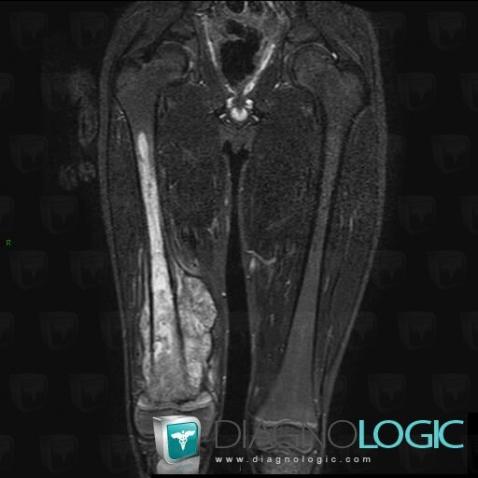

Osteosarcoma, Other soft tissues/nerves - Thigh, Femur - Mid part, MRI

- Diagnosis Osteosarcoma, Location(s) Other soft tissues/nerves - Thigh, with gamuts Soft tissue lesion with surronding oedema, Soft tissue mass with osteolysisFemur - Mid part, with gamuts Bone marrow replacementFemur - Distal part, with gamuts Bone marrow replacement